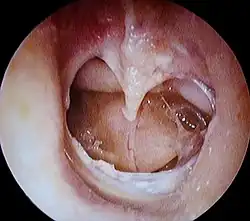

Trommelfellperforation

Eine Trommelfellperforation (bzw. Trommelfellriss) ist eine Pathologie des Mittelohres und des Warzenfortsatzes,[1] wobei ein Loch oder ein Riss im Trommelfell entsteht. Ein Trommelfellriss wird durch Mittelohrentzündung und/oder verschiedene Verletzungen verursacht, u. a. kann auch Geräusch eine Perforation provozieren.[2]

Diagnose

Eine Otoskopie (Ohrenspiegelung) bzw. Ohrmikroskopie dient dazu, mögliche Verletzungen und Entzündungen des Trommelfells zu erkennen.[8]